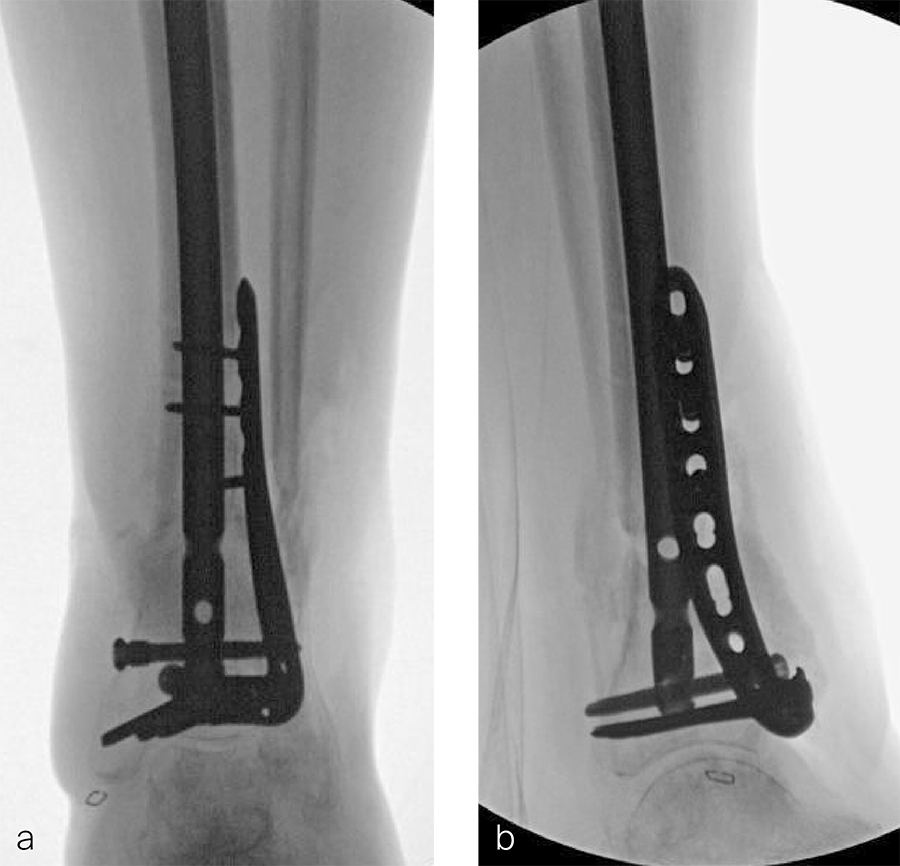

A 59-year-old man working for the city of Tulsa suffered an open distal tibia plafond fracture on the left leg when he fell into a sewer hole with raw sewage (Fig 1). The wound was grossly contaminated, and he was taken immediately to the operating room (OR) for incision and drainage and application of a spanning external fixator. Bone loss was noted anterior and medial (about 2.5 or 3 cm) but only about 2025% of the bone circumference.

After repeated incision and drainage, 2 days later the fracture was repaired with an anterior lateral tibial plafond plate (Fig 2). Vancomycin and tobramycin impregnated antibiotic beads were placed in the bone defect.

The patient was discharged on hospital day 6 to a rehabilitation facility with his left lower extremity in a splint and touch down weight bear allowance. He returned 2 weeks later with drainage from the medial traumatic wound. In addition, he had a gastrointestinal bleed from use of nonsteroidal antiinflammatory drugs. Once the gastrointestinal bleed was stabilized, he was taken the next day to the OR for another incision and drainage. Further, more significant, devitalized bone was resected, and an antibiotic cement spacer was placed (Fig 3). Deep culture samples were taken despite knowing the antibiotic resorbable beads had been placed in the wound at the time of initial closure. The plate was left in place, but a planned exchange plate/nailing was to be performed pending final culture results.

Two months later, the patient had a staged cement spacer removal and hardware removal followed by a new spacer placement (Fig 4). When microbiological cultures were negative for 5 days he was taken to the OR for definitive fixation and bone grafting. RIA bone graft from the ipsilateral femur was taken, a new anterior lateral plate was placed with an adjunct IM nail (and angle stable screws) as the distal plafond was now one articular block (Fig 5).